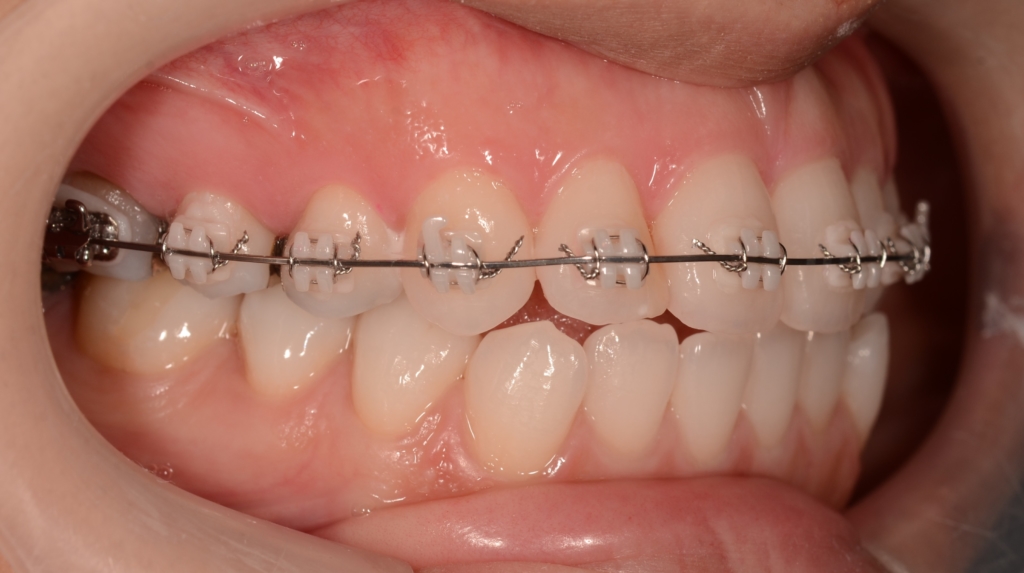

マルチブラケットシステム(スタンダードtype)で矯正を開始。

前歯部の噛み合わせに目途が付いた時点で、下の歯にも装置を付けて、合わせて治療を進めます。

噛み合わせがしっかりしたところで、上下とも第一小臼歯を抜歯して前歯を後方へ最大限に引っ込めて行きます。